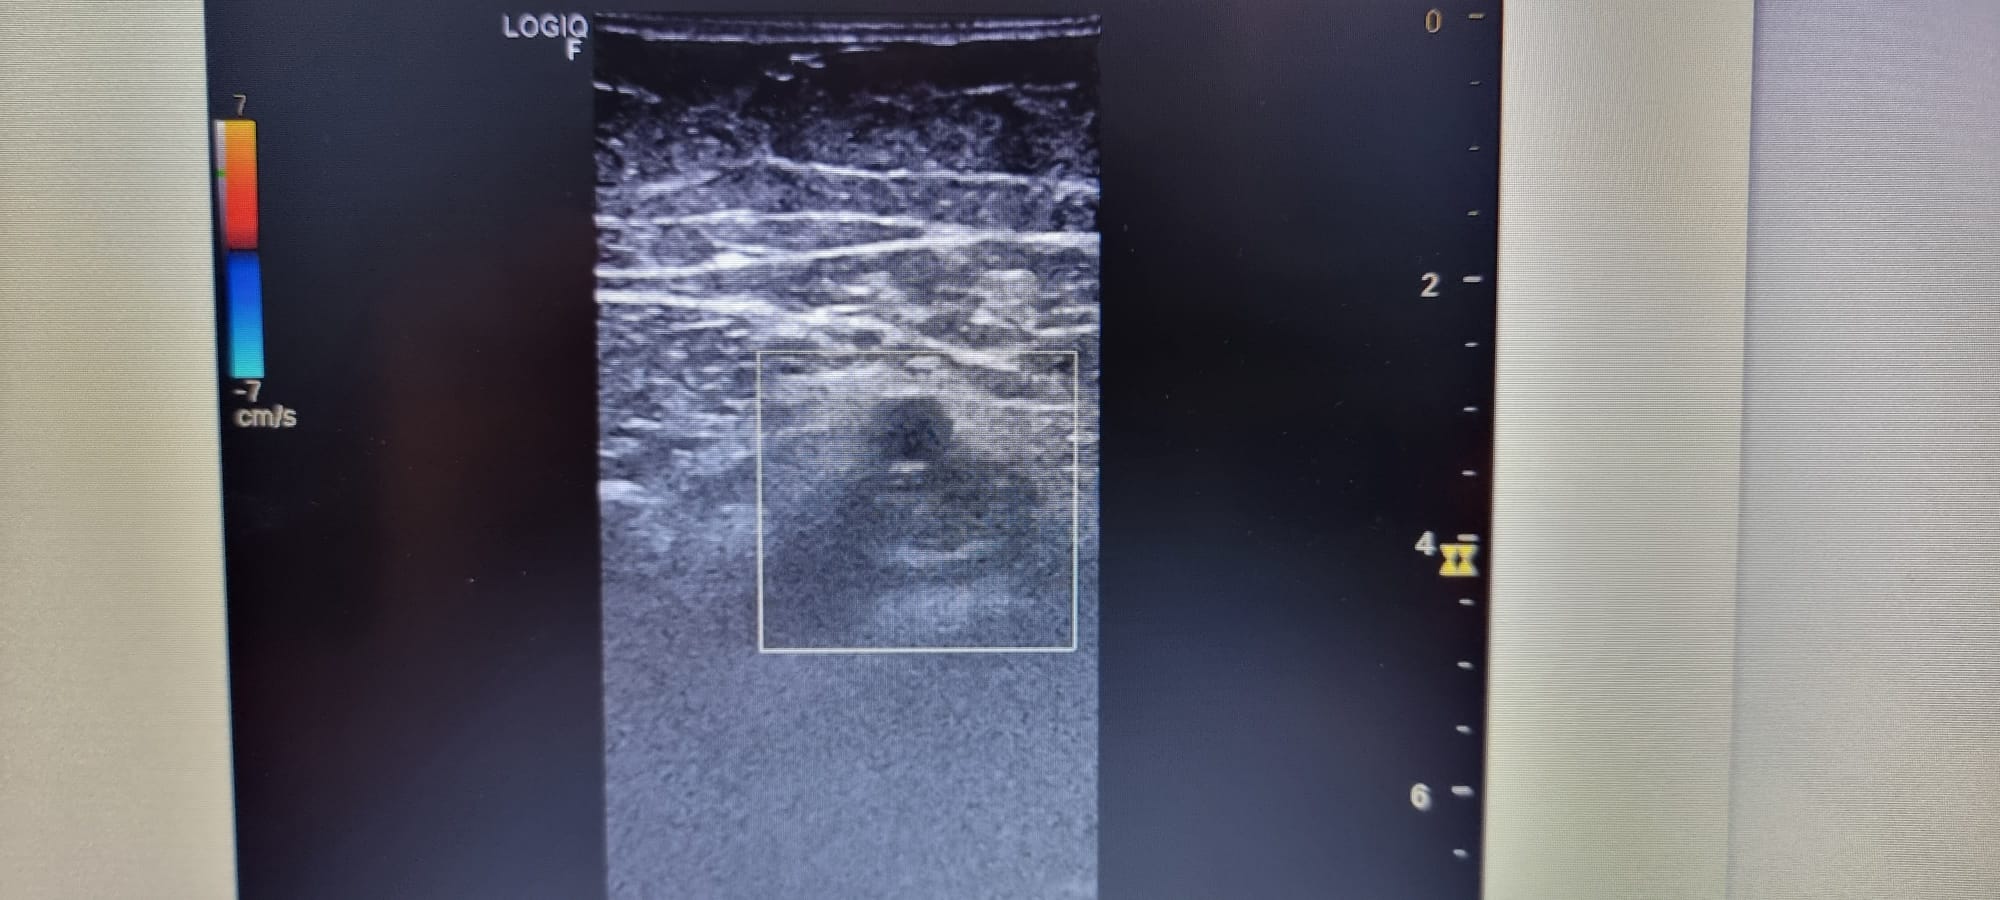

Hallazgos ecográficos

Se realiza ecografia venosa de mid evidenciándose ocupación parcial de femoral común, y segmento de femoral superficial.